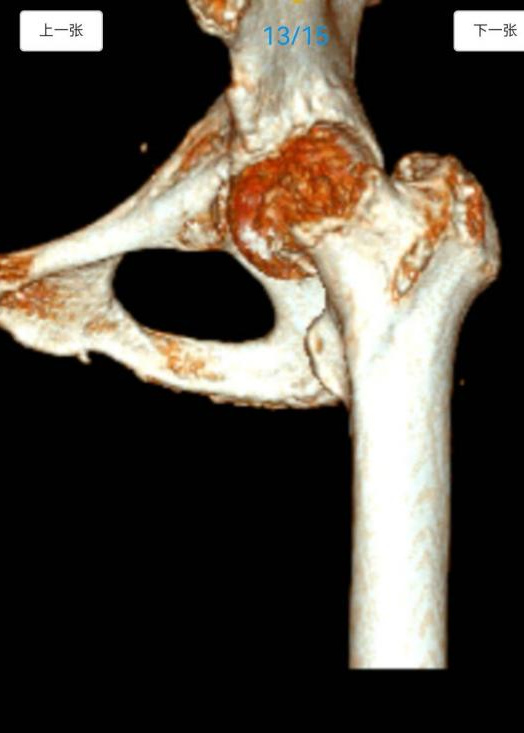

医院骨科徐信龙主任联合麻醉手术科、心内科、呼吸与危重症医学科、老年医学科等专家,开展多学科会诊(MDT),全面、细致地评估王奶奶的身体状况。评估结果不容乐观,一是老人生理机能退化,心肺储备能力差,B超提示心包积液,若不及时处理,可能导致心脏压塞,直接危及生命,而长期卧床又易引发肺部感染、深静脉血栓等严重并发症;二是老人基础病较多,长期服用多种药物,需调整用药方案以避免术中、术后风险;三是术后恢复难题,高龄患者伤口愈合慢,易出现感染、血栓、压疮等并发症。面对“先处理心脏问题还是先解决骨折”的两难局面,骨科、心内科、麻醉手术科等多学科专家共同评估后认为,需先通过心包穿刺引流术解除心脏压迫,待患者生命体征稳定后,再进行人工股骨头置换术。

心内科团队率先行动,王琛主任在超声引导下为患者实施心包穿刺引流术,精准抽出积液,患者胸闷、气促症状明显缓解,心脏功能得到改善。骨科团队针对王奶奶的基础疾病,提前制定输血、抗血栓、感染预防等预案。护理团队指导老人进行呼吸功能锻炼和床上排便训练,做好心理辅导缓解其焦虑情绪。